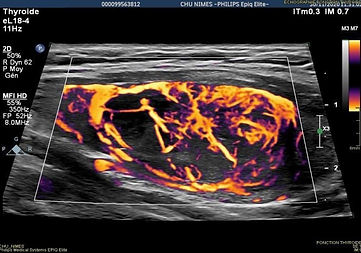

la vascularización

Valor controvertido en la literatura, la vascularización no se conserva en el sistema EU TIRADS.

La vascularización proporciona pocos argumentos diagnósticos, sin embargo en nódulos sólidos isoecoicos > 20 mm con fuerte vascularización central aumenta el riesgo de cáncer folicular, por otro lado una vasculatura periférica disminuye el riesgo.